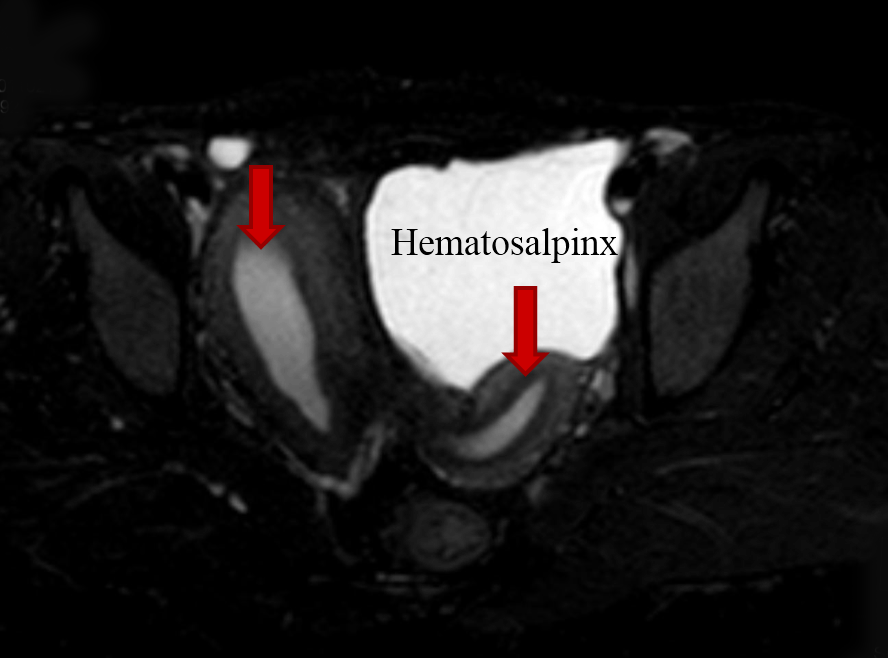

On local examination pubic hair were present, Tanner stage V. On speculum examination cervix was normal but deviated to left. On bimanual examination same mass was felt from right fornix and small size uterus from left fornix. Ultrasonography revealed bicornuate uterus with collection within endometrial cavity of right horn likely non-communicating. Bulky right ovary with a tract noted from it to the scar site on anterior abdominal wall likely scar endometriosis with solitary left kidney. Magnetic resonance imaging scan revealed two uterine cavities with a single cervix and vagina and a left communicating horn and a right non-communicating uterine horn with hematometra and right hematosalpinx (Figure 2). Blood filled tract was extending from the hematosalpinx to the skin opening on the anterior abdominal wall (Figure 3). Patient and her family were counseled and prognosticated about poor fertility potential. She was given the option of excision of the horn. Patient wished to retain her menstrual and child bearing function. She was taken up for laparotomy. Intra operatively fistulous tract was delineated with a probe (Figure 4) and a hypoplastic communicating uterine horn was identified. A right non-communicating normal sized uterus was present.

Figure 2: Magnetic resonance imaging scan showing two uterine cavities with a single cervix and vagina with a left communicating horn and a right non-communicating uterine horn with hematometra and right hematosalpinx.